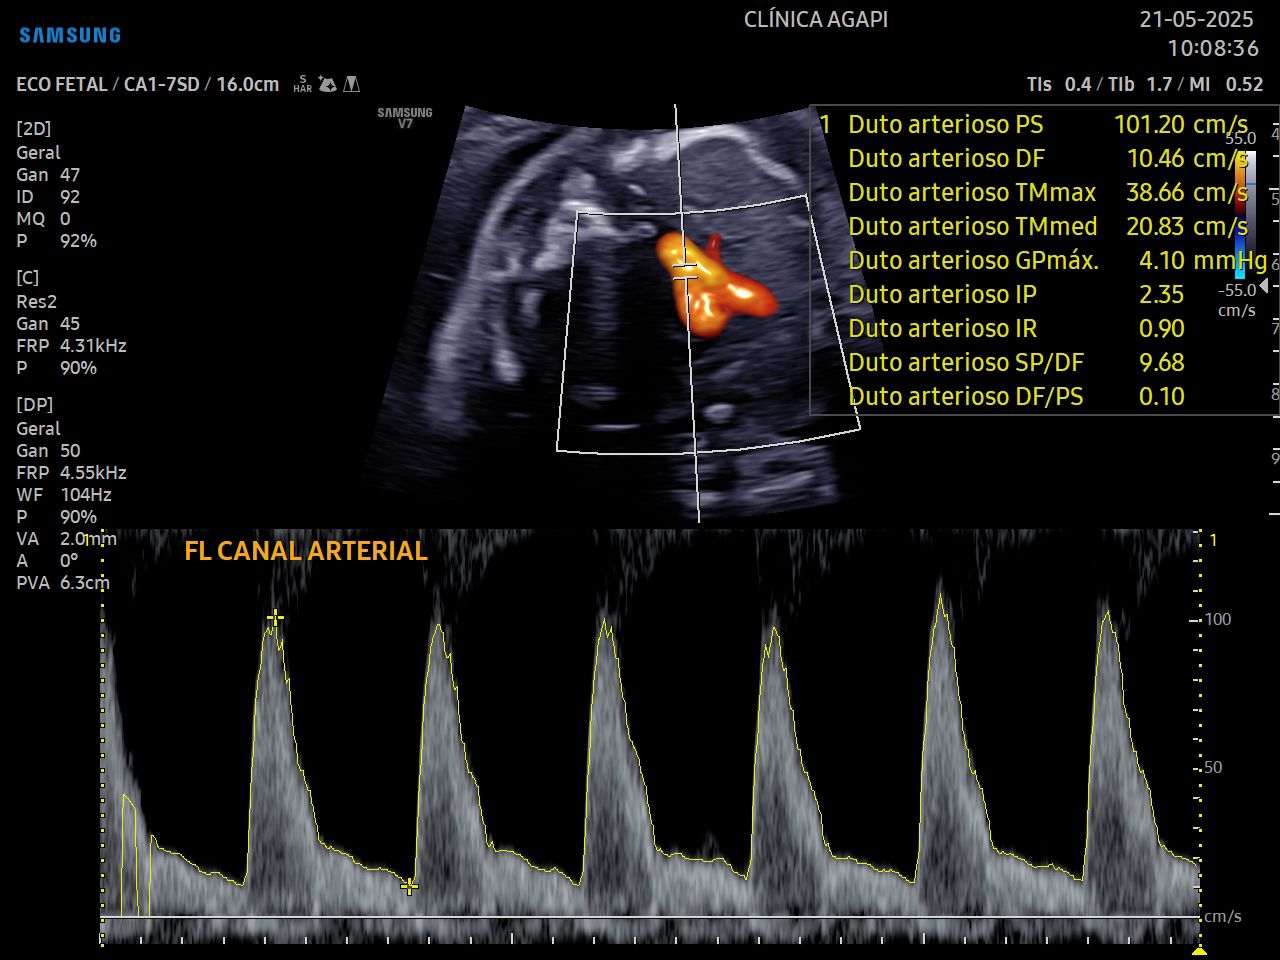

Esse exame é realizado por cardiologista pediátrico e avalia detalhadamente o coração do bebê e suas funções. As cardiopatias congênitas representam a principal causa de mortalidade perinatal por doença congênita e ocorrem com uma prevalência 8 a 12 casos por mil nascidos.

Deve ser realizado preferencialmente entre 26 e 29 semanas de gestação.